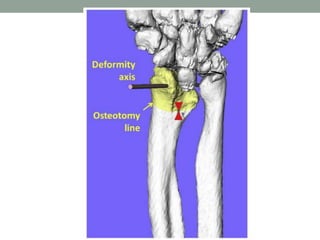

Nuestro proyecto . . .

• Pacientes con deformidad de Madelung

• Físis cerrada

• TAC

• Planificación preoperatoria

• Guías personalizadas para osteotomía